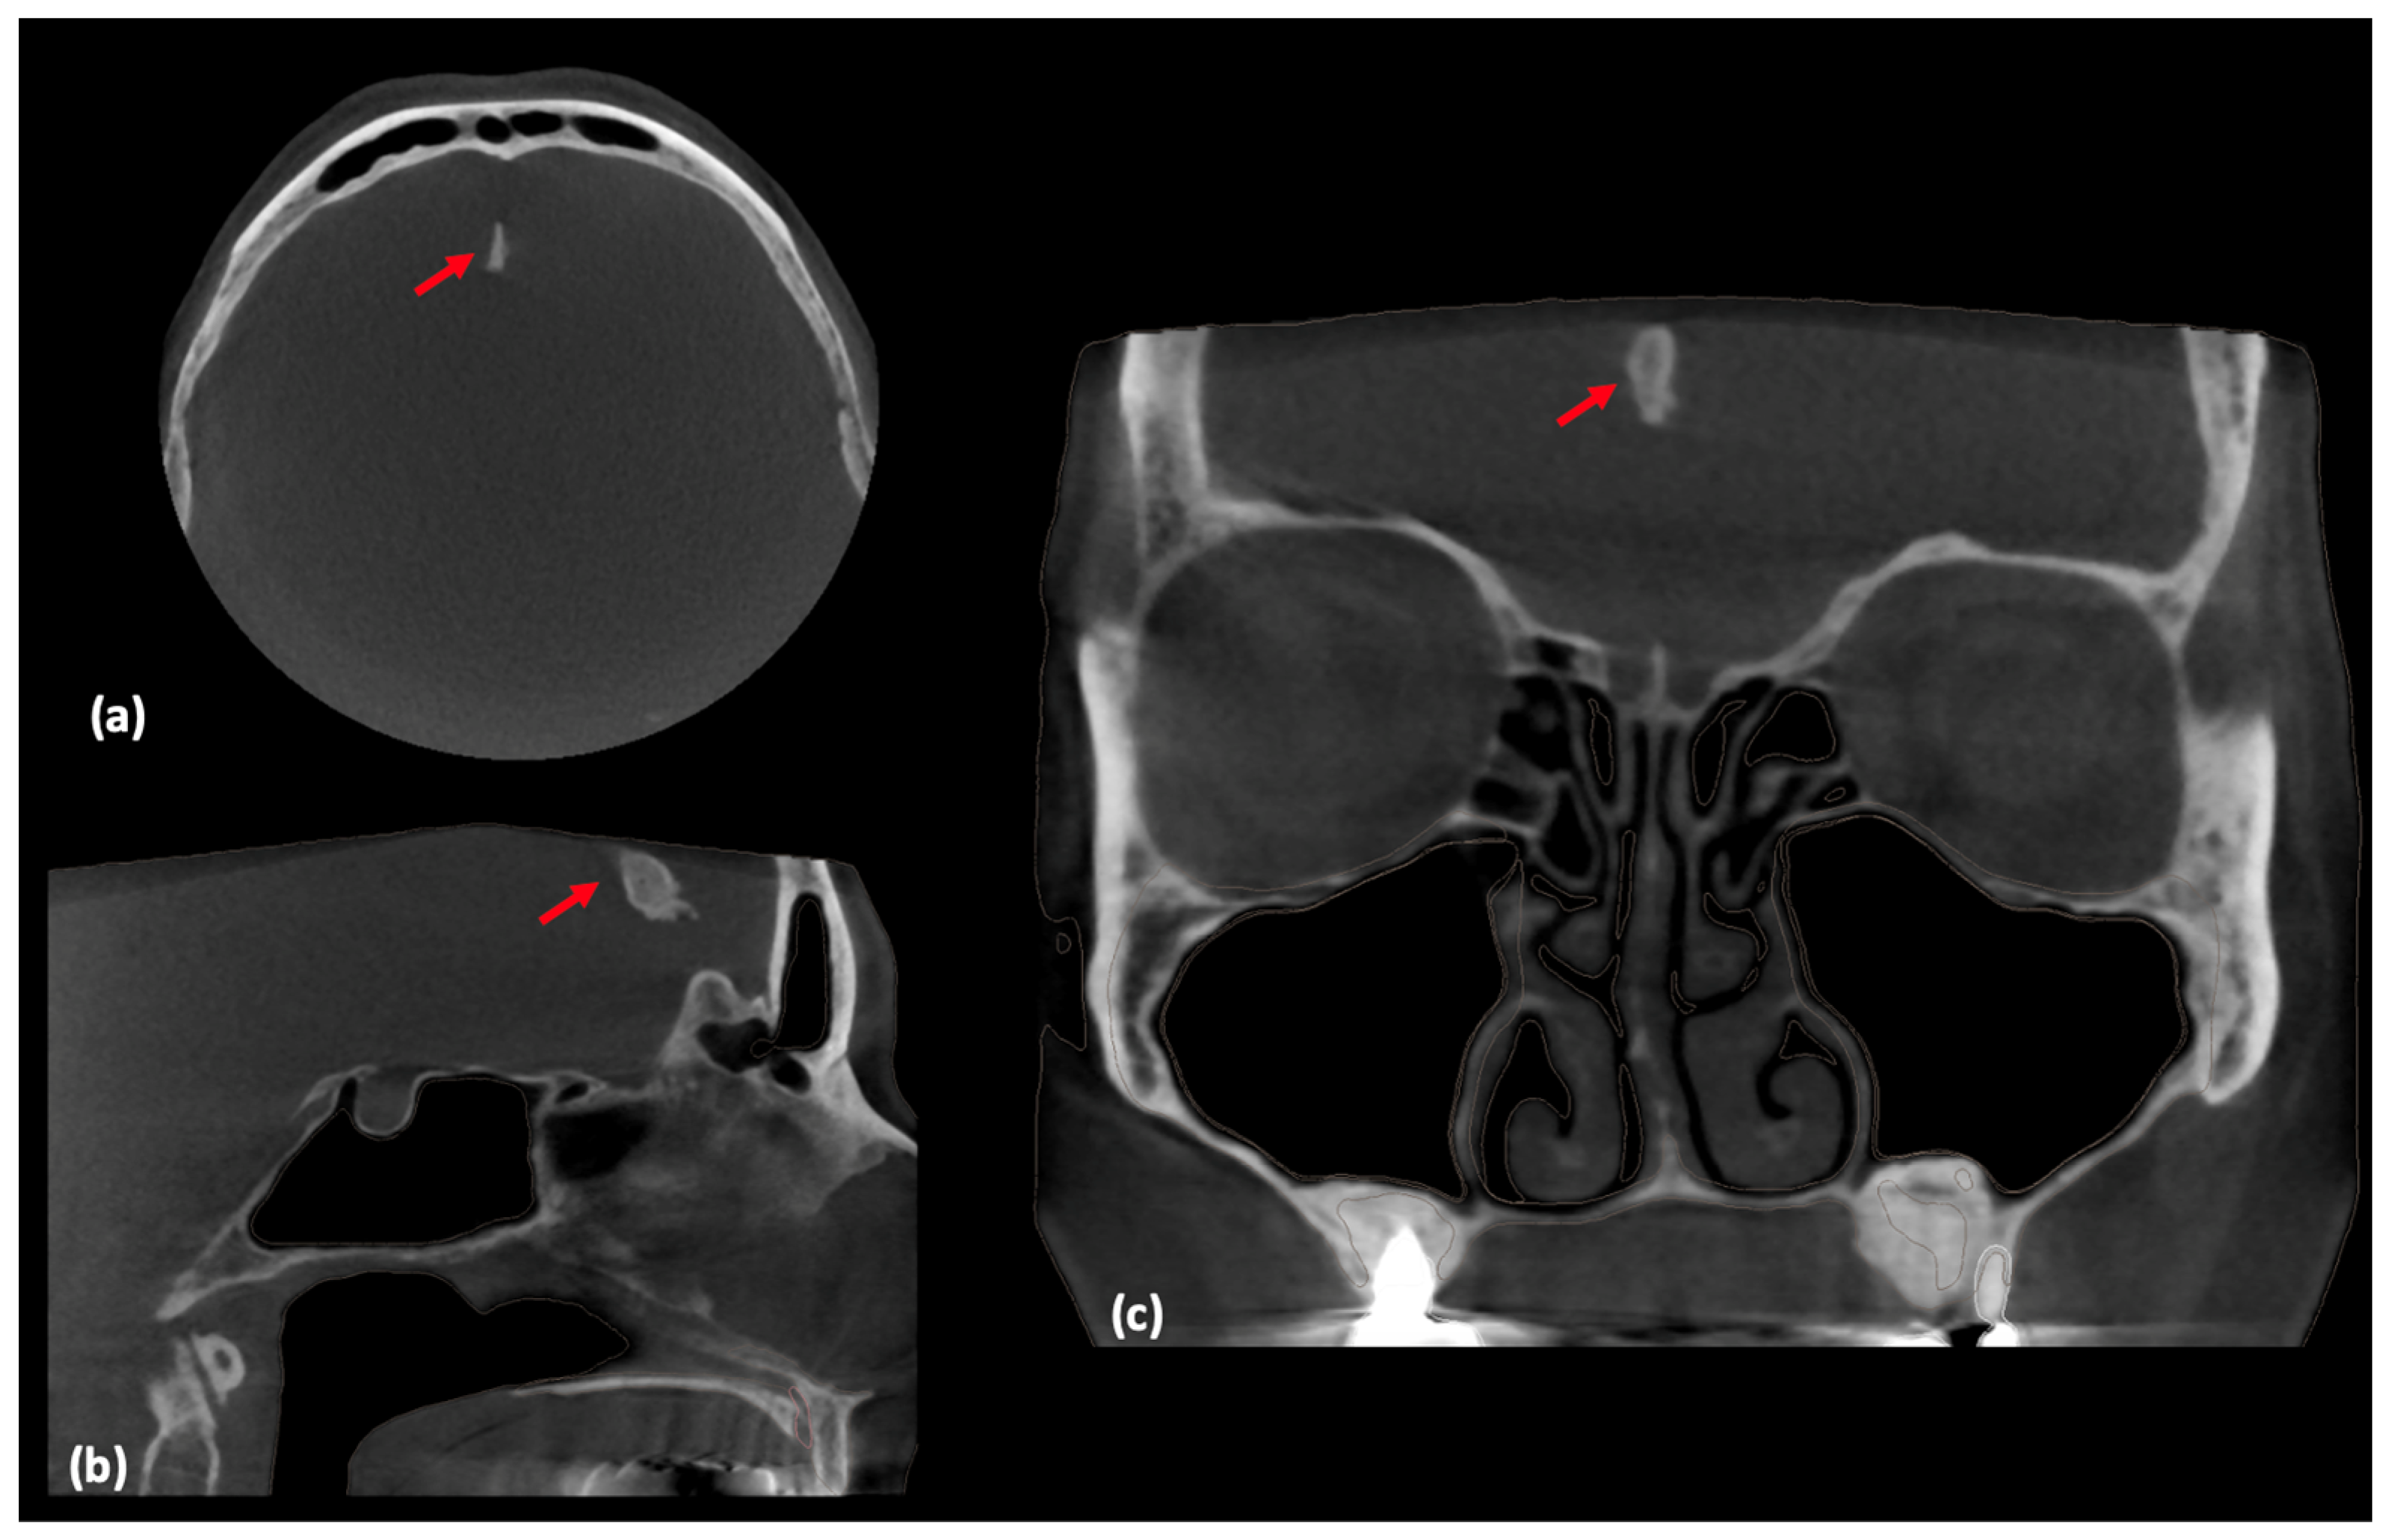

2. Case Report and AI Application